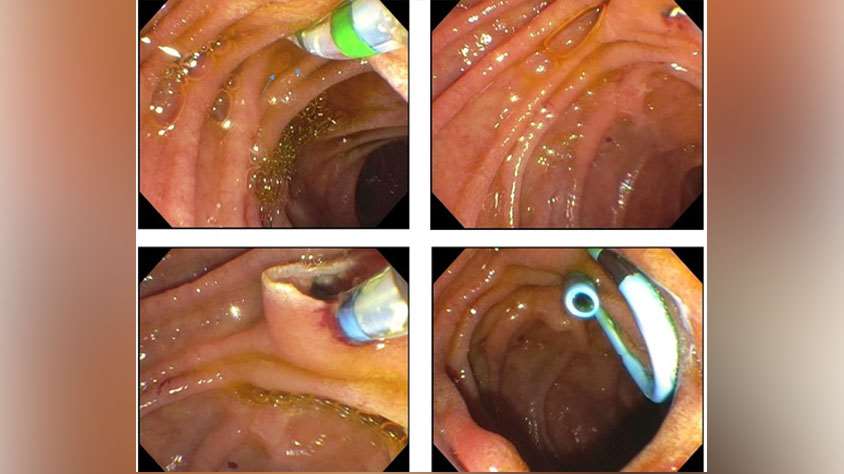

Our faculty have expertise in a wide variety of endoscopic techniques and procedures. The trainee should expect to receive hands-on experience in several procedures and techniques including routine and complex ERCP (e.g. cholangioscopy, pancreatoscopy, hilar biliary obstruction, lithotripsy, ampullectomy), diagnostic EUS, interventional EUS (including transmural drainage of pancreatic fluid collections, celiac ganglion block/lysis, EUS-guided biliary access and drainage, EUS-guided gastroenterostomy), complex resection of large colorectal polyps (including EMR and ESD), enteral stenting, management of leaks and fistulae, endoscopic eradication therapy for Barrett’s esophagus (EMR, RFA), and deep small bowel enteroscopy (single balloon only).